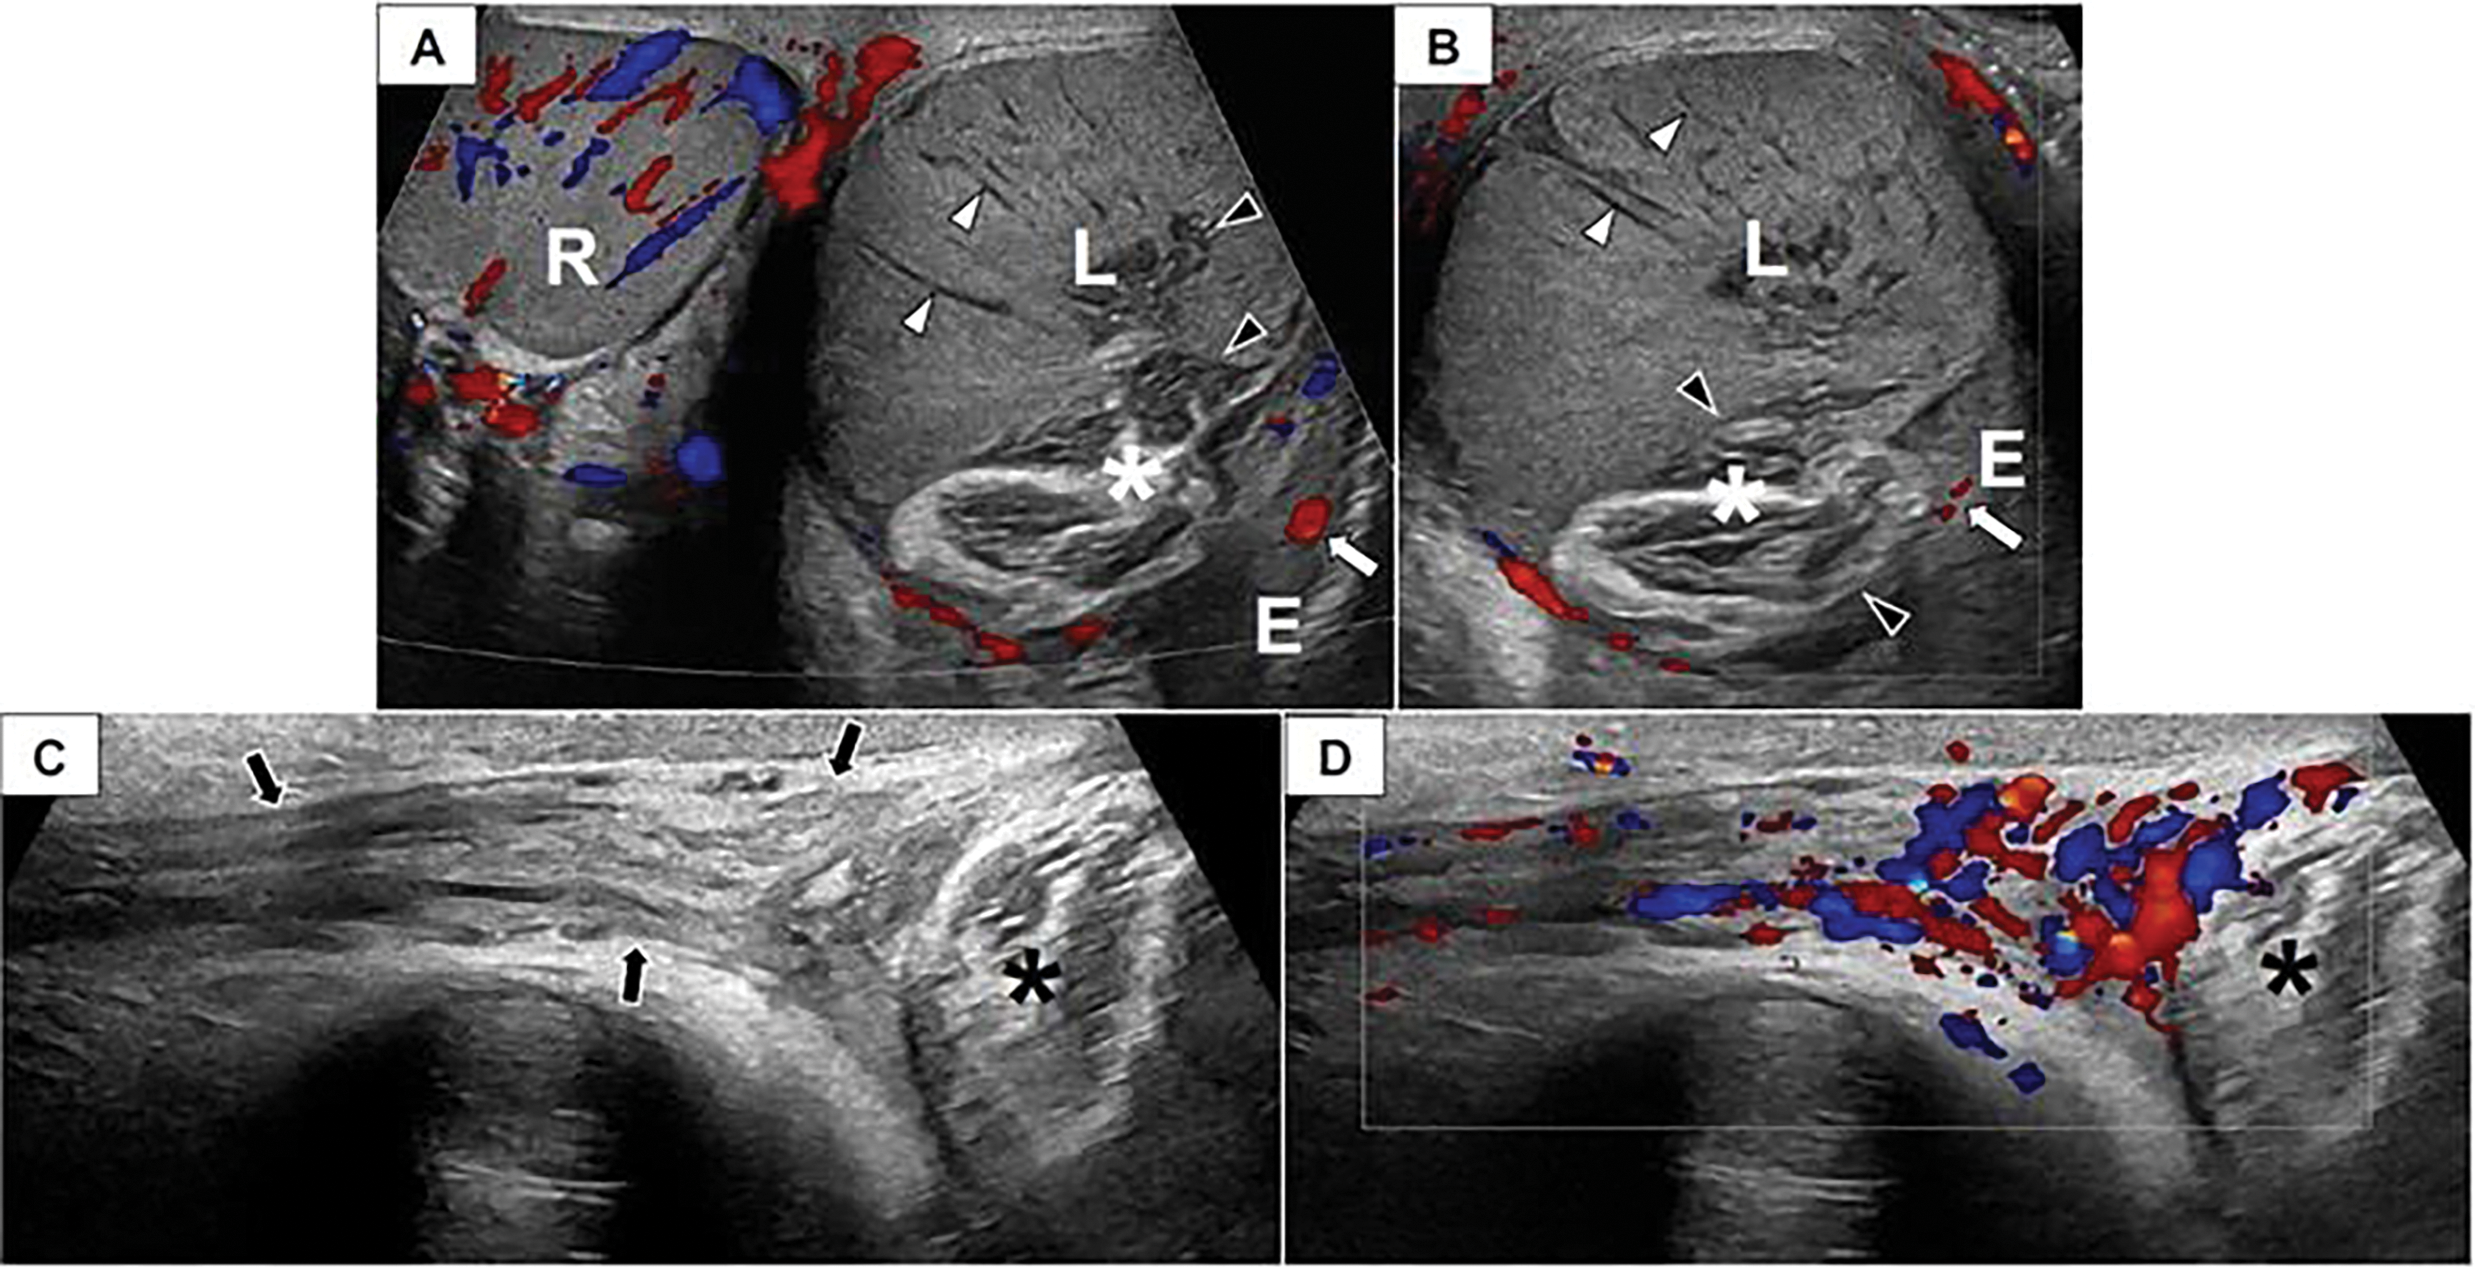

Physical examination revealed a palpably normal right testis and a non-tender, painless left testis the size of a peach, with the scrotal skin firmly adherent to the inferior aspect of the testis. Scrotal ultrasound with Doppler revealed an enlarged, heterogeneous left testis with peripheral hyperemia but without internal blood flow (volume of 41 mL), raising concern for either a torsion with a late, non-viable presentation or a testicular malignancy (Figure 1). The right testis appeared normal and well-perfused (volume of 25.2 mL).

FIGURE 1. Scrotal doppler ultrasound. Paratesticular venous malformation in a 14-year-old male. Transverse color Doppler image of the scrotum (A) and longitudinal color Doppler image (B) of the left hemiscrotum depict a normal, well-perfused right (R) testis. The left (L) testis is enlarged and avascular with linear hypoechoic structures (white arrowheads) extending radially from the testicular periphery toward the mediastinum that may represent thrombosed vessels. There is a lobulated structure (asterisk) interposed between the epididymis (E) and the left (L) testis that consists of bundles of hypoechoic parallel linear lucencies surrounded by echogenic fibrofatty tissue. This structure appears to insinuate itself into the testicular mediastinum (black arrowheads). The epididymis has a normal appearance and demonstrates perfusion (white arrow). (C) A longitudinal grayscale image depicts a normal, non-twisted left spermatic cord (arrows) that appears well-perfused on (D) color Doppler evaluation. Asterisk, venous malformation.